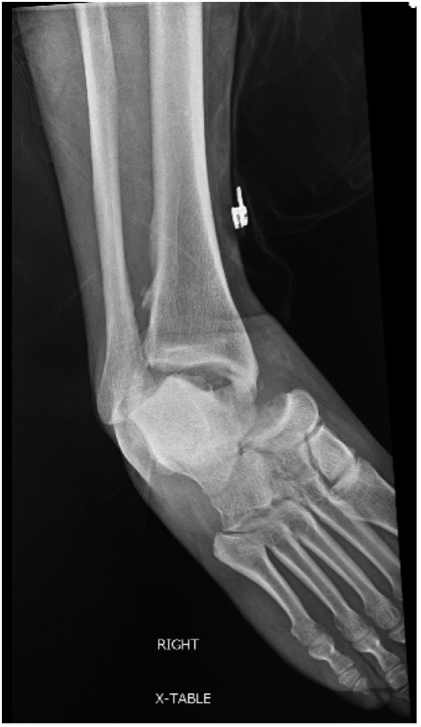

One should obtain plain film radiographs in the emergency department (Figure 1 above) prior to reduction and then following reduction. Multiple postreduction views should confirm proper position of the tibiotalar, subtalar, and talonavicular joints. Following reduction, computerized tomography (CT) scans may assist in identifying any residual intra-articular debris or articular irregularities.6,7 Additionally, one should consider CT results prior to taking the patient to the operative suite. Additionally, 3D-reconstructed CT scans may help scrutinize reduction and aid in surgical planning (Figure 2 below).

Plain film X-ray images (Figure 3 above) showed a pantalar dislocation at the subtalar (STJ), talonavicular (TNJ), and tibiotalar joints. The posterior portion of the fibula demonstrated a fracture. Computed tomography showed osseous debris in the posterior facet of the subtalar joint.

Following imaging, the patient underwent a hematoma block of the ankle and subtalar joint with lidocaine. Once properly anesthetized, we bent the knee and successfully reduced the deformity (Figure 4 above). Physicians applied a plaster splint for stability and admitted this patient for surgery the following morning. Surgeons felt the subtalar joint had residual instability. Additionally, the osseous debris in the posterior facet of the subtalar joint was difficult to ignore.